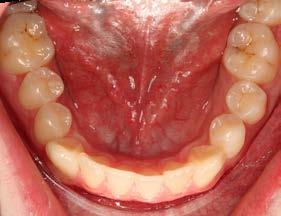

Las fotografías intraorales muestran las relaciones molares clase II y las relaciones caninas clase II bilaterales (Figura 3 y 4), espaciamiento anterosuperior, un overjet y overbite aumentado (Figura 5). La forma de los arcos es cuadrada, superior e inferior, con el apiñamiento moderado inferior y los espacios en superior.

Se planteó la corrección del perfil facial, corrección de las relaciones esqueléticas, corrección de overjet, overbite, del apiñamiento mandibular y cierre de espacio anterosuperiores; obtención de la clase I molar y canina bilateral, realizar las exodoncias de los terceros molares 18, 28, 38 y 48. Se realizó en una fase prequirúrgica de alineación, nivelación, (descompensación dental), tripodismo (estabilidad oclusal) utilizando brackets Roth .022 × .028, bandas en 6's y 7's

superiores e inferiores y vástagos quirúrgicos (Figura 6).